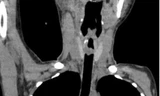

BS-CKII Nguyễn Thanh Hải, khoa Mũi xoang của BV Tai Mũi Họng TPHCM cho biết, trên kết quả chụp CT-Scan ghi nhận, bệnh nhân bị u xơ mạch vòm vùng mũi bên trái (kích thước khoảng 10x3cm). Khối u lớn đã phá hủy vách xương, lan rộng vào hố chân bướm khẩu cái bên trái, lan ra hố dưới thái dương đồng thời xâm lấn vào hốc mắt bên trái.